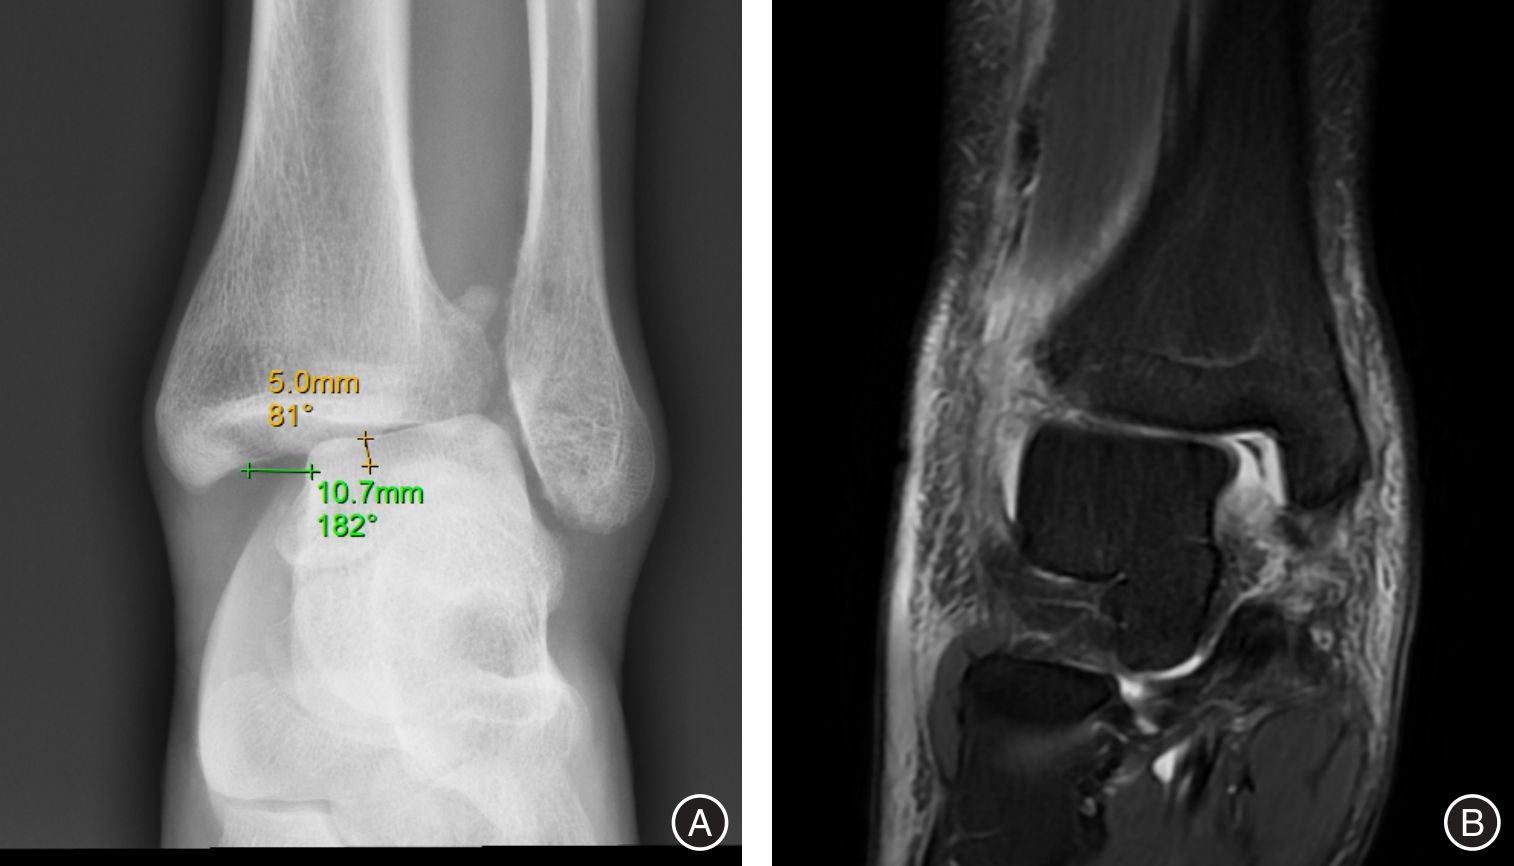

目的 探讨带线锚钉重建三角韧带(deltoid ligament)对踝关节骨折合并韧带损伤患者多维运动功能的影响。 方法 采用回顾性研究方法,纳入2023年3月至2024年3月期间在医院接受切开复位内固定术治疗的DL损伤合并关节骨折患者共210例。根据是否接受三角韧带重建分为重建组(110例)和对照组(单纯骨折固定,100例),其中重建组失访4例,对照组失访2例。比较两组术后优良率,并于术前及术后3、6、12个月评估六自由度(Six Degrees of Freedom,6DOF)运动参数、美国足踝外科协会评分(AOFAS)、疼痛视觉模拟评分(VAS)及影像学指标(间踝间隙和距骨倾斜角),同时记录术后并发症发生率。 结果 重建组手术时间、术中出血量和住院时间均显著高于对照组(P < 0.001)。术后12个月,重建组优良率显著高于对照组(93.40% vs. 81.63%,P < 0.05)。两组术后所有评估指标随时间持续改善,且重建组在踝关节6DOF运动参数(内旋/外旋、背伸/跖屈、内翻/外翻、上移/下移、内移/外移、前移/后移)、AOFAS评分及VAS评分方面改善程度均优于对照组(P < 0.001)。影像学结果显示,重建组间踝间隙及距骨倾斜角恢复更佳(P < 0.001)。两组术后并发症发生率差异无统计学意义(P > 0.05)。 结论 在关节骨折合并三角韧带损伤的治疗中,带线锚钉重建三角韧带可有效改善踝关节运动功能,提高AOFAS评分,减轻疼痛,促进影像学复位,且不增加术后并发症风险,是治疗此类损伤的安全有效方法。

Objective To investigate the impact of deltoid ligament reconstruction using suture anchors on multidimensional motor function in patients with ankle fractures combined with ligament injuries. Methods A retrospective cohort study included 210 patients undergoing open reduction and internal fixation (ORIF) for ankle fractures with confirmed DL injuries between March 2023 and March 2024. Based on intraoperative management of the DL, patients were allocated to a reconstruction group (received suture anchor-based DL reconstruction, n = 110; 4 lost to follow-up) or a control group (ORIF alone without DL reconstruction, n = 100; 2 lost to follow-up). Outcomes assessed preoperatively and at 3, 6, and 12 months postoperatively included: 6DOF ankle motion parameters (internal/external rotation, dorsiflexion/plantarflexion, inversion/eversion, superior/inferior translation, medial/lateral translation, anterior/posterior translation), American Orthopaedic Foot & Ankle Society (AOFAS) scores, visual analogue scale (VAS) pain scores, and radiographic parameters (medial clear space, talar tilt angle). Clinical efficacy at 12 months and postoperative complication rates were also compared. Results The reconstruction group demonstrated significantly longer operative times, greater intraoperative blood loss, and longer hospital stays compared to the control group (all P < 0.001). At 12-month follow-up, the excellent and good rate (based on AOFAS) was significantly higher in the reconstruction group (93.40% vs. 81.63%, P < 0.05). While all parameters improved significantly over time in both groups, the reconstruction group exhibited significantly greater improvements in all 6DOF motion parameters, higher AOFAS scores, and lower VAS scores at all postoperative time points (all P < 0.001). Radiographically, the reconstruction group achieved significantly better restoration of the medial clear space and talar tilt angle at all postoperative assessments (all P < 0.001). Postoperative complication rates did not differ significantly between the groups (P > 0.05). Conclusion For patients with ankle fractures combined with deltoid ligament injuries, suture anchor-based anatomical reconstruction of the deltoid ligament effectively restores multidirectional ankle kinematics, improves functional outcomes as measured by the AOFAS score, alleviates pain, and facilitates radiographic reduction, without increasing the risk of postoperative complications, thereby representing a safe and effective treatment strategy.